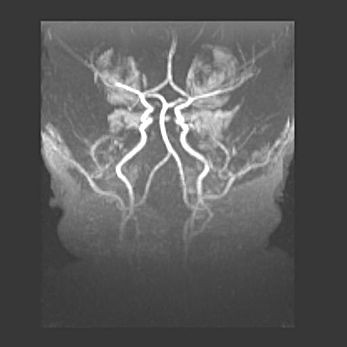

Открытая гидроцефалия.

Возраст: 6 месяцев 15 дней

Вес: 6200 г

Пол: женский

Окружность головы: 41 см

Срок гестации: 38 недель

Гидроцефалия головного мозга у новорожденных – это скопление избыточного количества цереброспинальной жидкости в головном мозге. Ее избыточное скопление в мозге приводит к патологическому расширению желудочков мозга (четырех полостей, расположенных в глубине белого вещества мозга, заполненных цереброспинальной жидкостью и связанных узкими проходами).

Открытый тип гидроцефалии (сообщающаяся) наблюдается тогда, когда нарушен механизм всасывания ликвора в системный кровоток. При этом типе причиной заболевания чаще всего является перенесенные ранее инфекции (например: менингит),  либо же наличие крови в субарахноидальном пространстве.